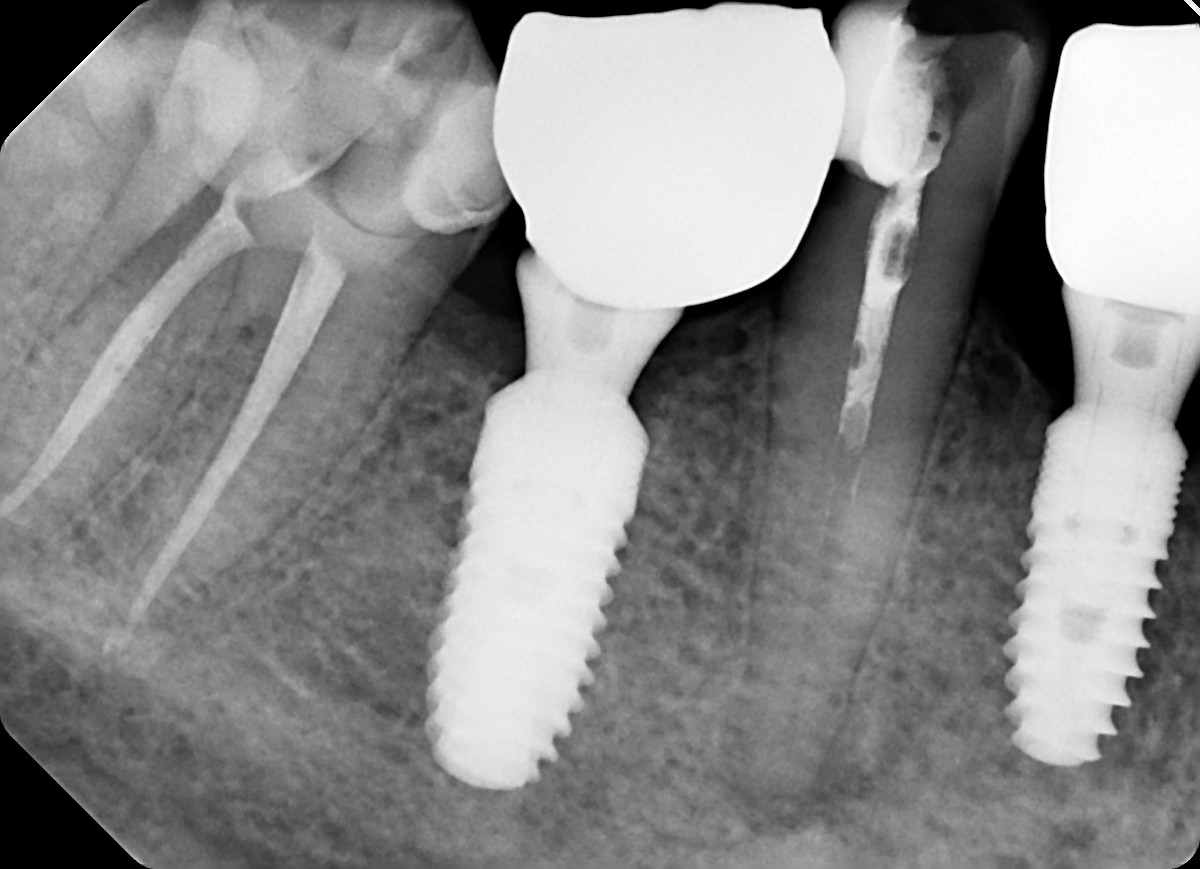

22. What option can be selected for the crown over the implant?

25. What option can be selected for the crown over the implant?

28. What option can be selected for the crown over posterior implant?